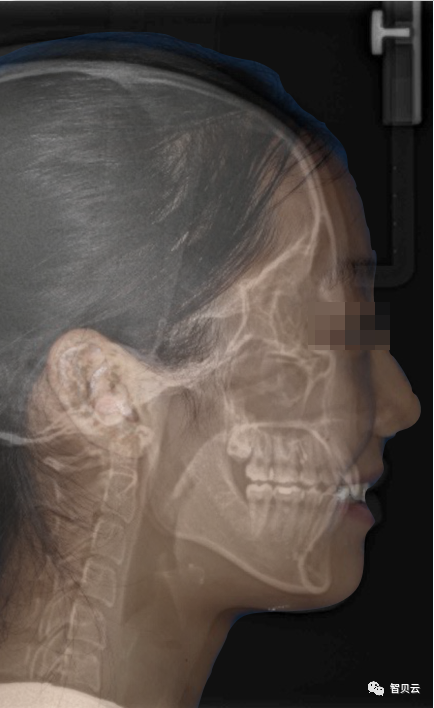

_PRE-TXNorm FMIA°47°55.0SNA°77.7°83.0SNB°70.2°80.0ANB°7.5°3.0FMA° 29.826PFH/AFH70.5°70Z Angle°50.3°77U1-FH113.0110.0IMPA°103.297.0U Lip to s’ line6.3 mm5.0L Lip to s’ line3.9 mm3.0OP-FH1215

头侧位片:

▲下颌后缩,骨性Ⅱ类

▲高角,颏部发育不足

▲上下前牙唇倾

Post-TXPRE-TXPost-TXNormFMIA°47°57.555.0SNA°77.7°76.883.0SNB°70.2°73.780.0ANB°7.5°3.13.0FMA° 29.828.026PFH/AFH70.5°65.970Z Angle°50.3°64.477U1-FH113.0103.7110.0 IMPA°103.291.197.0U Lip tos’ line6.3 mm3.25.0L Lip to s’ line3.9 mm1.03.0OP-FH1212.615